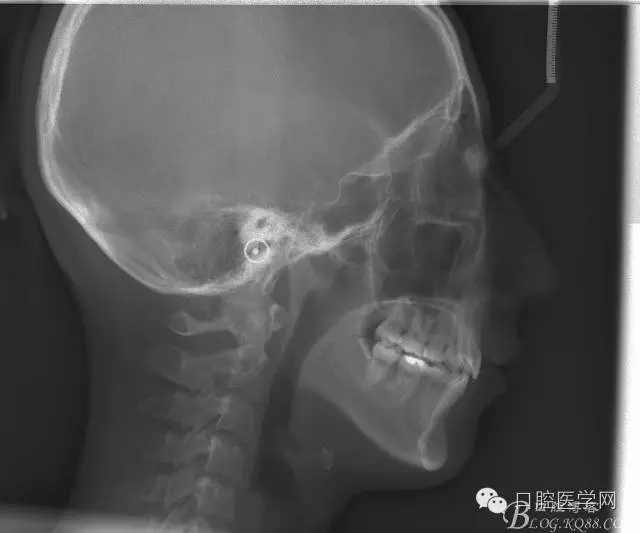

查:右側(cè)第二前磨牙第一乳磨牙恒尖牙頰側(cè)前庭溝隆起,捫有乒乓球感。曲斷及CT示:右側(cè)第二前磨牙第一乳磨牙恒尖牙根尖區(qū)有一囊腫,頰舌側(cè)骨板極薄,牙根無吸收,第二前磨牙牙根位于囊腫中,第一雙尖牙牙冠遠(yuǎn)中水平向阻生,牙冠位于囊腫中。經(jīng)協(xié)議:手術(shù)摘除創(chuàng)傷大,同意開創(chuàng)引流保守治療。

正畸查:替牙合。第一恒磨牙中性合。上牙弓尖圓型下牙弓方圓型。前牙覆合3度覆蓋7.5mm。下前牙咬到上舌側(cè)牙齦。上頜擁擠4.0mm,下頜擁擠

3.0mm。上頜稍前突下頜后縮,上下唇前突,上前牙覆蓋下唇,下唇外翻。面下三分之一過短,頦唇溝明顯,開唇露齒,頦饜窩明顯。顳下頜關(guān)節(jié)開閉口無彈響,無壓痛,開口型開口度正常。

正畸前后頭顱側(cè)位SN平面和S點(diǎn)重疊圖: